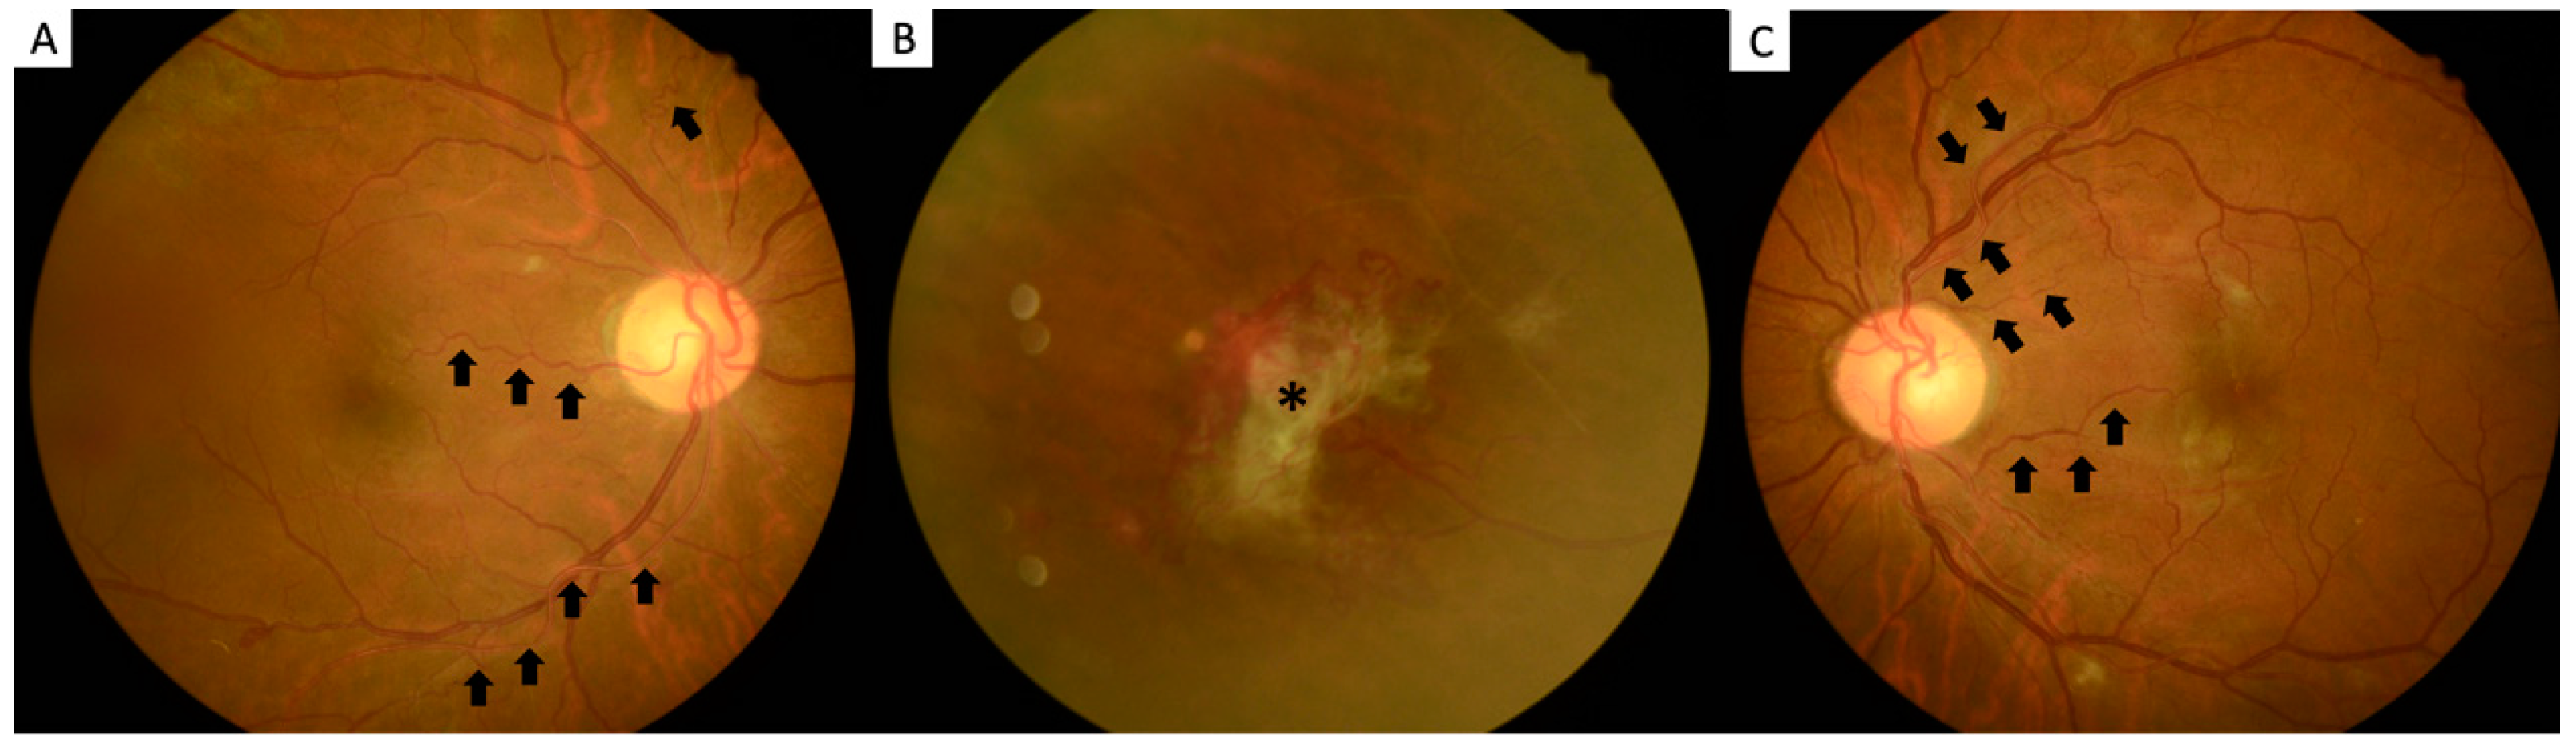

Polycythemia-Related Proliferative Ischemic Retinopathy Managed with Smoking Cessation: A Case Report

2. Case Report